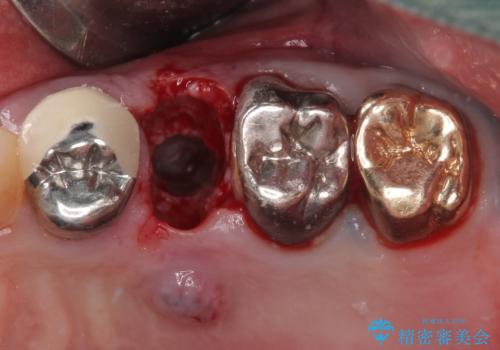

破折した奥歯 抜歯即時埋入インプラントによる補綴治療

- 舌側に膿の出口がずっと消えずに有り続けることを気にして来院された患者様です。

目視で歯根が破折していることが分かり、保存不可能と判断されたたため、抜歯即時埋入インプラントによる補綴治療を行うこととしました。

抜歯即時埋入後にはずっと気になっていた排膿が消え、痛みも腫れも特になく、3ヶ月という短期間で無事に治療を終えることができました。